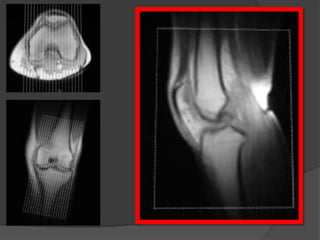

Colocado y centrado el paciente, comienza la secuencia de

localización. Dando imágenes en los tres planos: axial,

sagital y coronal

axial

sagital coronal